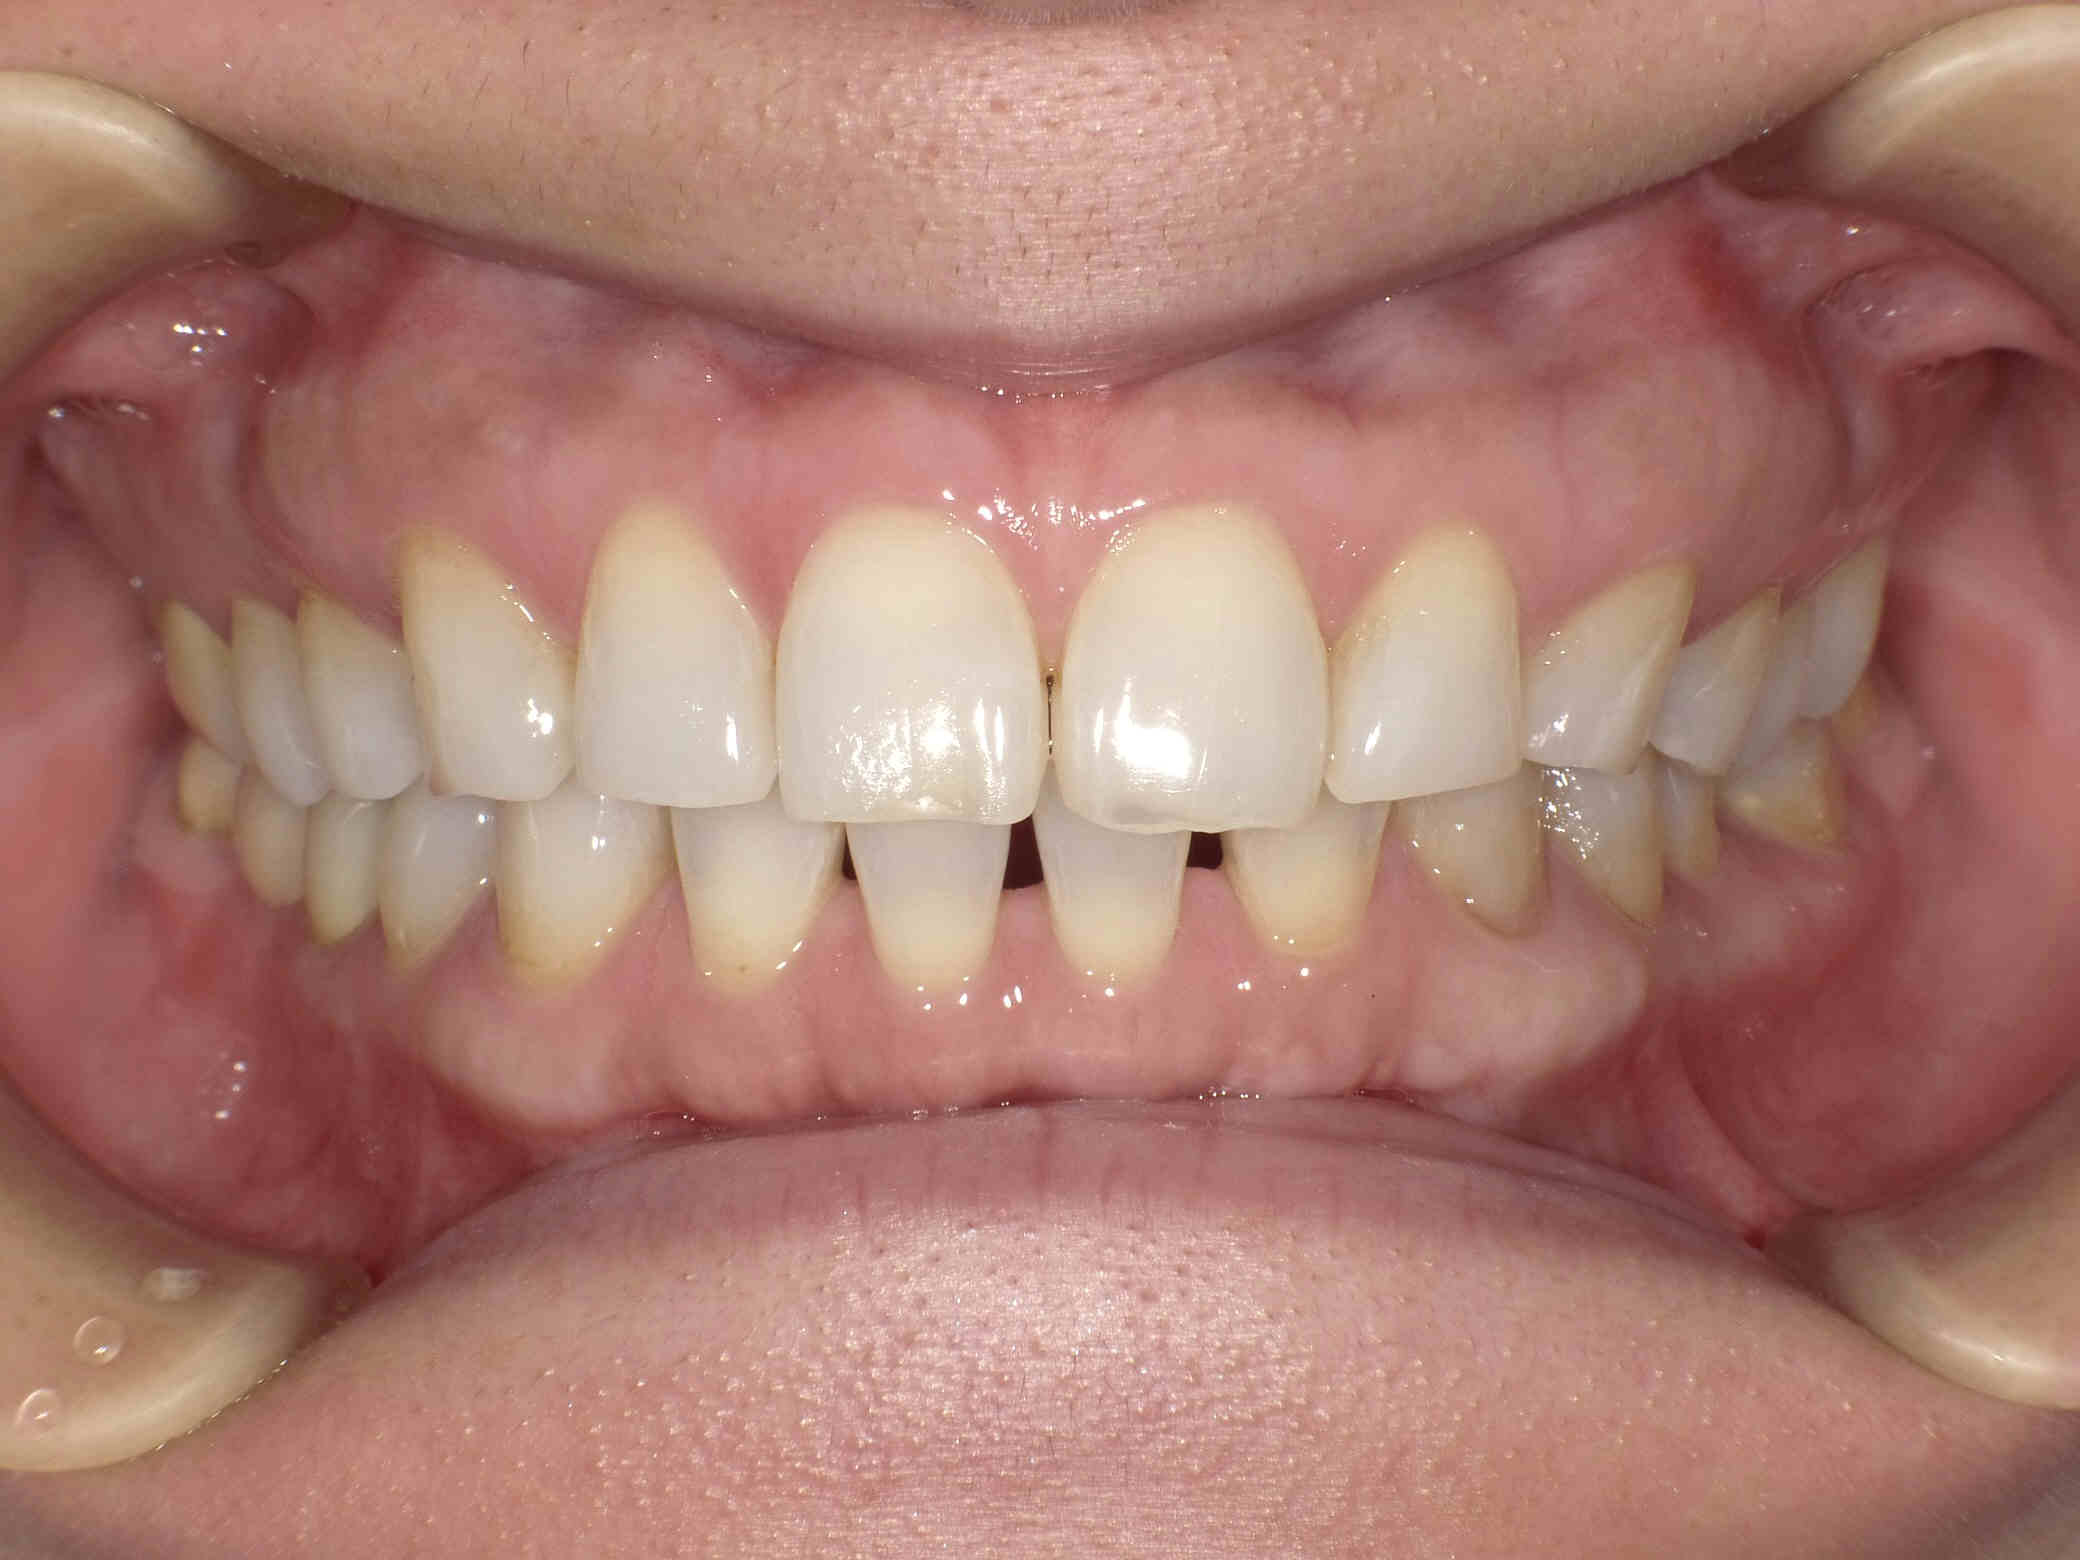

治療後

元々咬む筋力や食いしばり・歯ぎしりが非常に強く、『フレアーアウト』(前歯の歯並びが前方に放射状に倒れていく現象)によって「出っ歯」や「すきっ歯」の状態になっていました。

今回はご希望のマウスピース矯正で、食いしばりや歯ぎしりによる歯の破折やすり減りを予防しながら、歯と歯の隙間が広がって傾斜した前歯を元の位置に戻しました。

ホワイトニングも同時進行で施術し、白く輝く歯になりました。

元々入っていた臼歯のブリッジは治療せず、そのままの位置で矯正を行うことを希望されたため、正中(上顎と下顎の中心線)を合わせることは難しいですが、美しい歯列と口元へ仕上がりました!